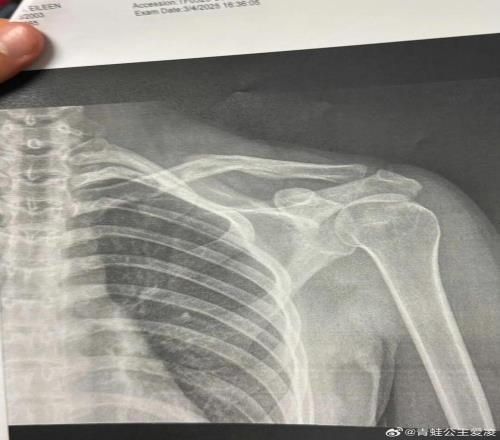

機會來了!NBA級全能內(nèi)線被曝離隊,廣東隊有望重金完成截胡